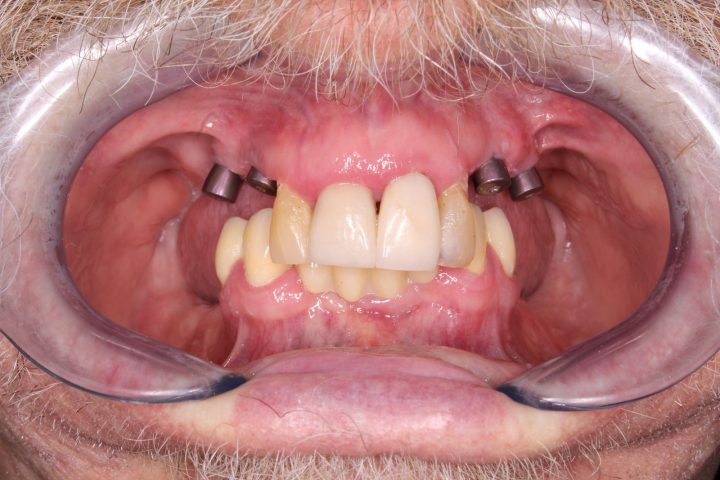

In der gleichen Behandlung hat er noch oben 4, und unten 6 Implantate bekommen, daneben hat er im Ablauf den 5 Tagen provisorischen Zahnersatz gekriegt.

Danach hatte er 4 Monate lange Heilungszeit, bald war den endgültigen Zahnersatz fertig: Oben wird eine Stegprothese auf 4 Implantate bearbeitet, unten wird eine Brücke auf 6 Implantate befestigt.